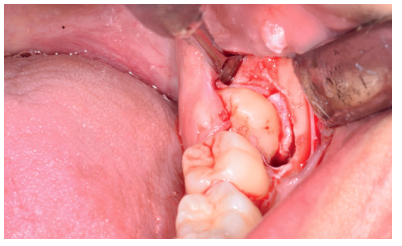

Caso clínico: se presenta un caso clínico de una mujer de 20 años, sin antecedentes médico-quirúrgicos de interés, que acudió a consulta remitida por su ortodoncista, para la extracción de un premolar maxilar retenido, en posición invertida. Tras la extracción del premolar y del tercer molar inferior retenidos, se obtuvo dentina procedente de ambos, para la regeneración ósea guiada del defecto resultante de la extracción del premolar, realizando revisiones a la semana y a los 4 meses de la intervención.

Clinical case: a clinical case of a 20-year-old woman is presented, with no interesting medical record, who went to dental clinic for removal of an inverse maxillary bicuspid retained. After maxillary bicuspid and lower third molar extractions, autogenous dentin was obtained from both teeth, to perform a guided bone regeneration of the bicuspid defect. A week and 4-month check-up were carried out.